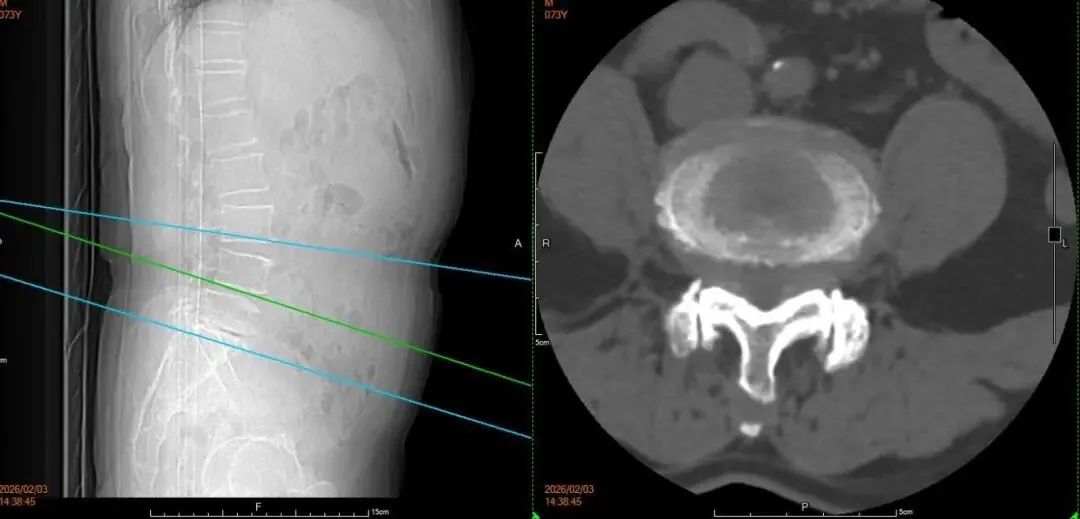

案例二:患者男,73岁,因“反复腰腿疼痛10年余,加重伴间歇性跛行2年”入院,入院诊断:1.腰椎椎管狭窄症2.腰椎滑脱3.腰椎间盘突出症。在全身麻醉下行后入路腰椎前柱融合术+腰椎间盘髓核切除伴椎板切除术+腰椎植骨术+L4/5脊髓神经根粘连松解术+2~3个椎骨融合或再融合+脊椎融合物置入术+腰椎脱位切开复位内固定术,术后恢复良好,患者及家属对治疗效果十分满意。